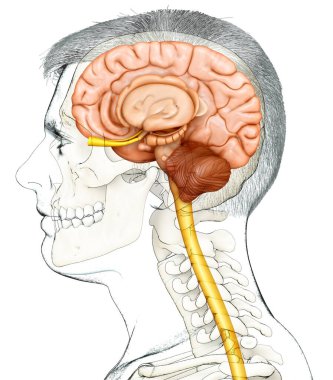

The arterial blood supply to the neck (carotids and vertebral arteries).